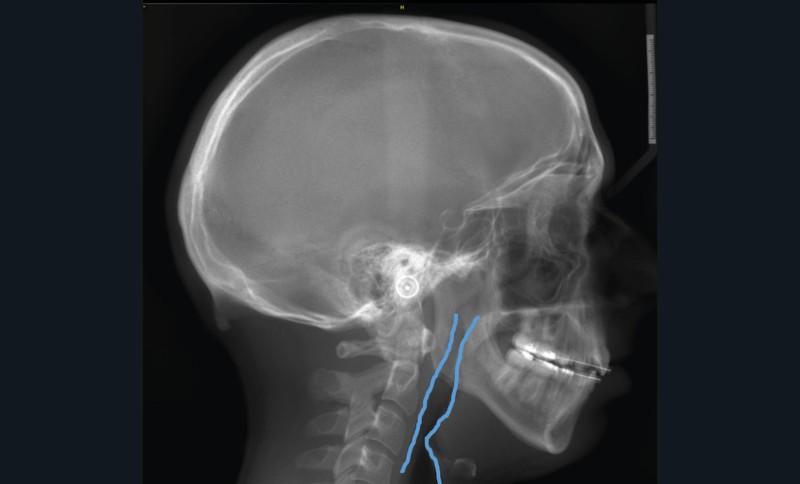

Le Dr François Cheynet et à nouveau le Pr Michel Le Gall (fig. 12) viendront plaider pour une prise en charge chirurgicale précoce de certains décalages squelettiques, afin de briser au plus vite la spirale dysmorpho-dysfonctionnelle et influencer le schéma de croissance postopératoire.